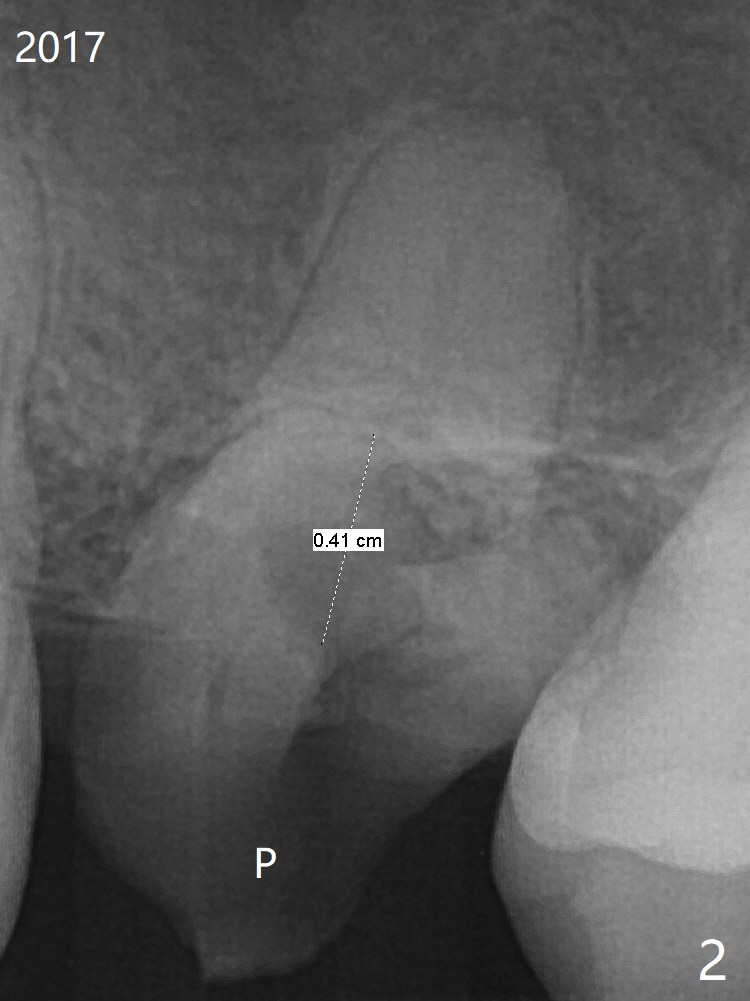

A 59-year-old nervous woman has poor dentition with upper left pain (Fig.1). Composite was placed at #12 and sedative filling at #13 two years ago. If the tooth #14 causes discomfort, it should be extracted for bone graft or immediate implant (Fig.4). PRF will be prepared (x2, white and red). The implant will be placed slightly palatal (P, Fig.2), since the residual buccal roots are more likely associated with buccal plate bone loss. If she agrees with treatment planning, take 5x5 cm CT for the bone loss and sinus. Sinus lift seems necessary because of short bone and septum (Fig.2,3).